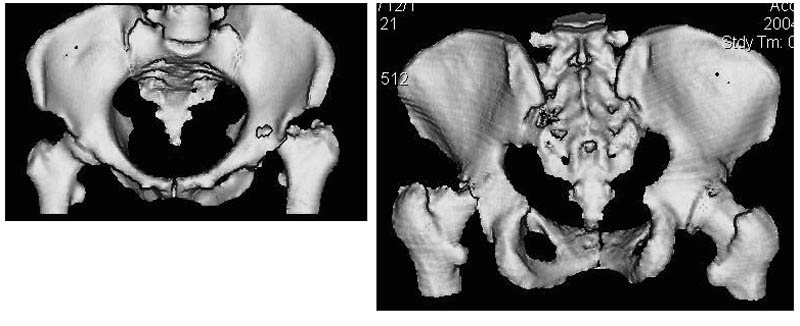

Женщина, 45 лет. В марте перенесла левосторонний коксит неизвестной этиологии. Специфику и онкологию исключили.

Интраартикулярных инъекций не было. Сейчас процесс клинически и рентгенологически - стабилизировался. Состояние вполне удовлетворительное.Предполагается тотальное эндопротезирование с пластикой полости аутокостью. Возможна ли бесцементная <чашка>? Заранее благодарю! С уважением,А.В.Владзимирский

Пртезирование через пол года после коксита закончившегося лизисом сустава, который на снимках выглядит как гнойный? Что значит неизвестной этиологии?

Уважаемый коллега! Последняя версия - мы пролистали ренгенологическую книженцию-так картинка вполне подходит под сустав Шарко (neuropatic joint ). В тазобедренном суставе патология редкая (но меткая). Ищите причину - варианты - нейросифилис, сирингомиелия, опухи спинного мозга (и выше тоже) компрессия спинного

мозга извне, рассеяный склероз, алкоголизм. А так-же : склеродерма ,Рейно,ревматоидный артрит, амилоидная инфильтрация нервов,и это не считая всяких менингеомиелоцеле,asymbolia,Riley-Day syndrom,и все возможные другие нейропатии. На данном этапе не спешите оперировать(протезирование протиопоказано при нейропатических суставах),проконсультируйтесь с классным невропатологом,сделайте МЯР головного озга и